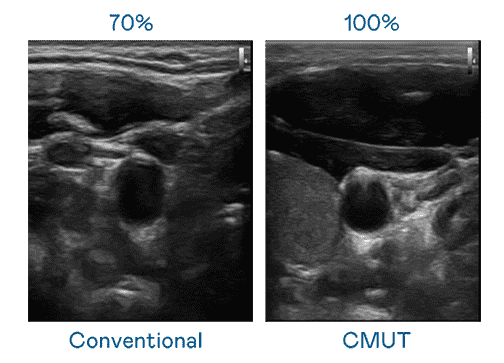

CMUT 技术是一种用电容式微机电元件来产生超音波讯号的技术。。。与传统 PZT 压电式技术相比,,,CMUT 频宽增加 30%,,,,更宽频的超音波讯号让影像解析度大幅提升,,,,是实现高影像品质医疗超音波扫描、、、促进精准医疗发展的关键技术。。

大频宽带来超清晰影像

超音波影像的解析度高低,,首先取决于探头能发出的讯号频宽。。。。人生就是博 CMUT 可提供高清晰的超音波讯号,,,提供高频宽、、高灵敏度、、、、影像纹理细节更高的超音波影像,,,,协助医护人员缩短影像判读时间及利用精准的医疗影像进行诊断。。